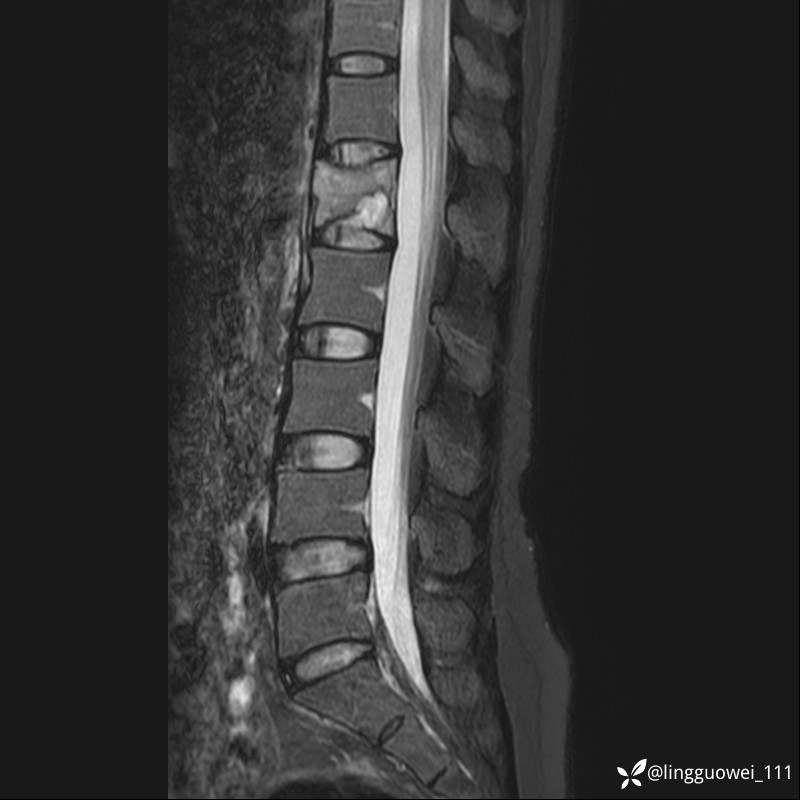

病例女,39岁,腰痛来诊,只有CT可能要鉴别诊断,而MR可以定性吗?

患者性别:女

患者年龄:39岁

主诉:腰痛

T1

T2

T2+FS